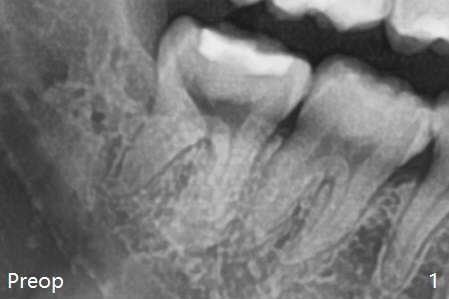

With incision, buccal trough is created at #32 for elevators so that the 2nd molar is not affected by elevation.  Collagen plug is placed in the socket to prevent dry socket (Fig.2).  The mesial socket is completely ossified (Fig.3 *), while the distal one partially ossified 4 months postop.  The ossification in the distal socket seems to be from coronal to apical (Fig.3 arrow), in contrast to the traditional thinking of apico-coronal.  The corono-apical growth may be related to Collagen plug placement.  The plug is probably not originally inserted into the distal apical region.